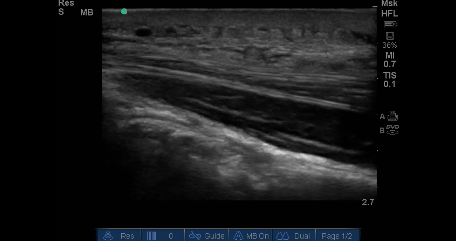

Cellulitis on musculoskeletal ultrasound Gepost op 27 december 2017 door netwerkvsseh Cellulitis on musculoskeletal ultrasound @theultrasoundsite.co.uk Dit delen: Delen op X (Opent in een nieuw venster) X Share op Facebook (Opent in een nieuw venster) Facebook Delen op LinkedIn (Opent in een nieuw venster) LinkedIn E-mail een link naar een vriend (Opent in een nieuw venster) E-mail Afdrukken (Opent in een nieuw venster) Print Vind-ik-leuk Aan het laden... Gerelateerd